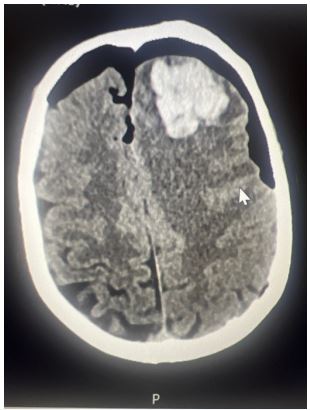

A 75-year-old man underwent elective bilateral revision FESS for recurrent right-sided nasal polyps. His history included a previous FESS in 2014 and burr hole drainage of a chronic subdural haematoma in 2019. Initial recovery was unremarkable. On the evening of surgery, he became confused, vomited coffee-ground emesis, and was noted to have right- sided weakness and facial droop. GCS was E4V4M6, BP elevated at 230/120 mmHg. A CT brain showed a left frontal intracerebral haemorrhage with pneumocephalus and a suspected breach of the ethmoid sinus.

Figure 1: Sociodemographic characteristics of pregnant women in Cotonou.